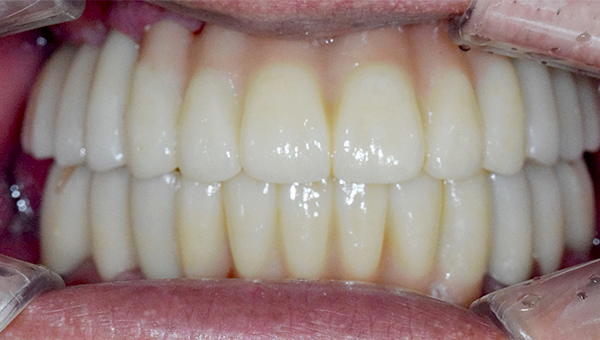

2025.05.30

치료 후